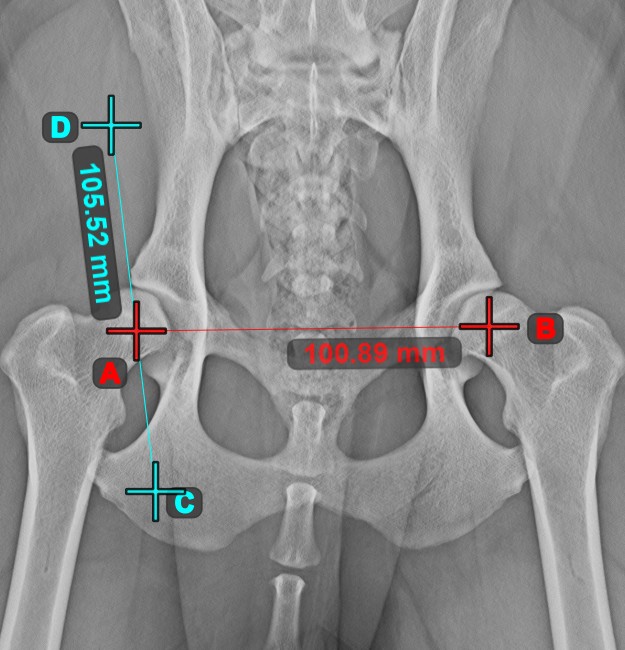

Linienmessung¶

Erstellen Sie eine Linienmessung, um den Abstand zwischen zwei Punkten mit hoher Genauigkeit zu berechnen.

Wählen Sie das Werkzeug Linienmessung

aus und weisen Sie es einer der verfügbaren Maustasten zu. Setzen Sie die Start- und Endpunkte in der Szene oder wählen Sie sie aus bereits vorhandenen Punkten im Bild aus. Der Abstand zwischen den beiden Punkten wird automatisch anhand der Standardkalibrierdaten oder der durch die Längenkalibrierung-Messung neu kalibrierten Daten berechnet.

Ändern Sie den Start- und Endpunkt mit dem Werkzeug Objekt auswählen/verschieben

. Der Abstand zwischen den beiden Punkten wird automatisch neu berechnet.